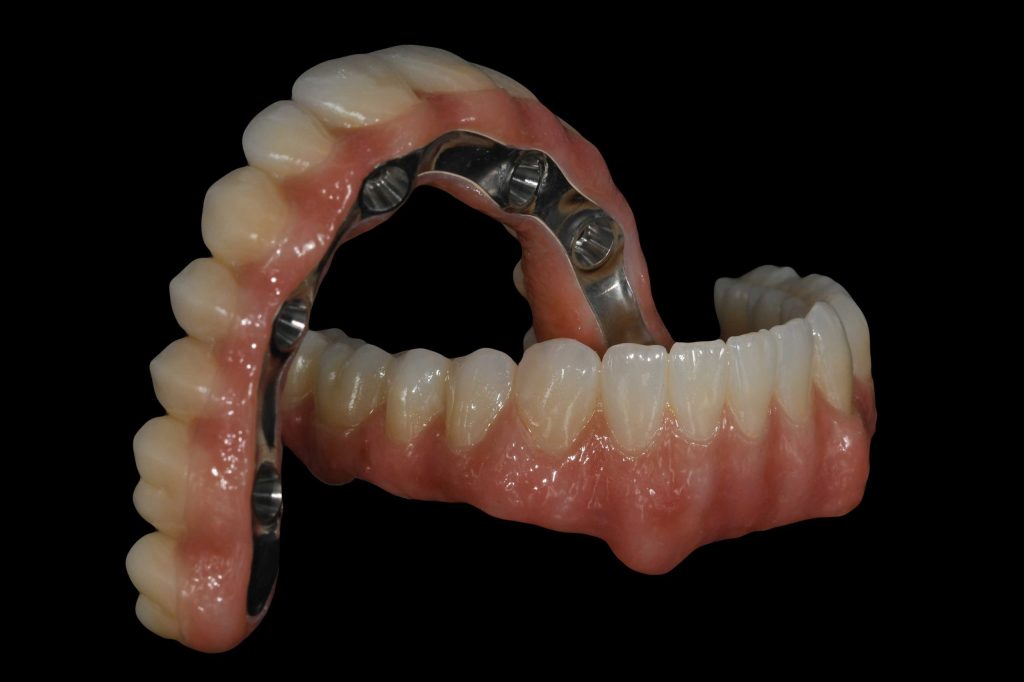

Коронки, мосты и полные протезы, изготовленные у нас

После того как импланты полностью проходят этап заживления, в Facialia мы сами выполняем финальную ортопедическую часть лечения. Это включает изготовление:

- коронок на имплантах

- мостов на имплантах

- полных протезов

Выполнение этого этапа в самой клинике позволяет нам тщательно контролировать каждую деталь окончательного результата и обеспечивать высокий уровень эстетики, функциональности и точности прилегания постоянной конструкции.

Реставрации из циркония: естественная эстетика и гарантия 5 лет

Финальные ортопедические конструкции, которые мы выполняем в нашей клинике, изготавливаются из циркония — материала, который высоко ценится за свой естественный внешний вид и хорошую биосовместимость. Кроме того, цвет подбирается индивидуально в соответствии с натуральным оттенком зубов пациента или, в случае полной реабилитации, с учётом его эстетических предпочтений.

Наша цель — чтобы окончательный результат был не только функциональным, но и гармоничным, комфортным и максимально естественным.

Кроме того, на эти циркониевые конструкции предоставляется гарантия 5 лет, что даёт пациентам ещё больше спокойствия и уверенности.